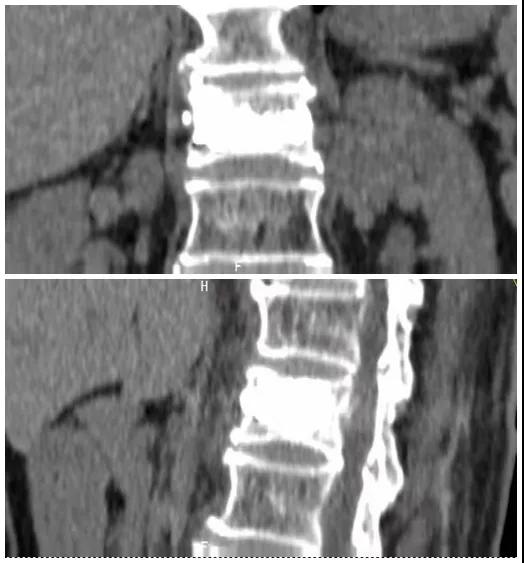

術(shù)后復查CT可見骨水泥彌散充分